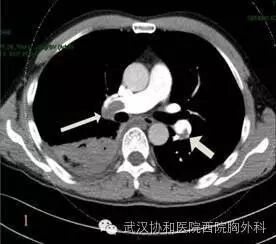

右心导管显示右室收缩压显著>主动脉收缩压,平均压>左心室压力,右室